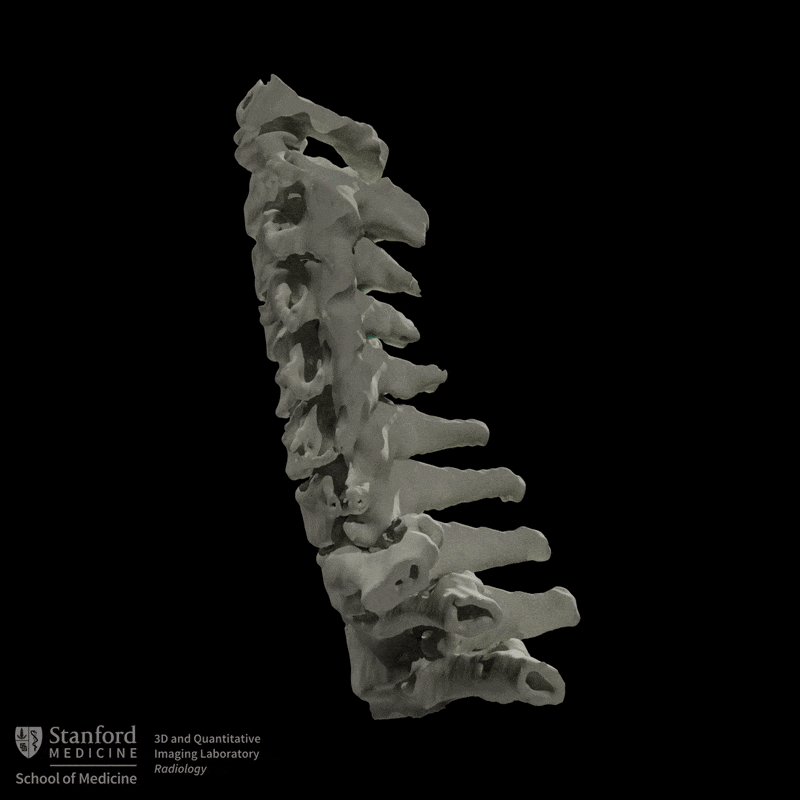

Using the CT dataset, a radiologic technologist processed the images to create a series of advanced visualizations that highlight the distribution of ossification and its relationship to surrounding anatomy. These images provide different perspectives of the cervical spine and help translate cross-sectional findings into more intuitive views.

Figure D: Grayscale rotational volume render of the spine.

Figure E: Grayscale rotational volume render of the spine.